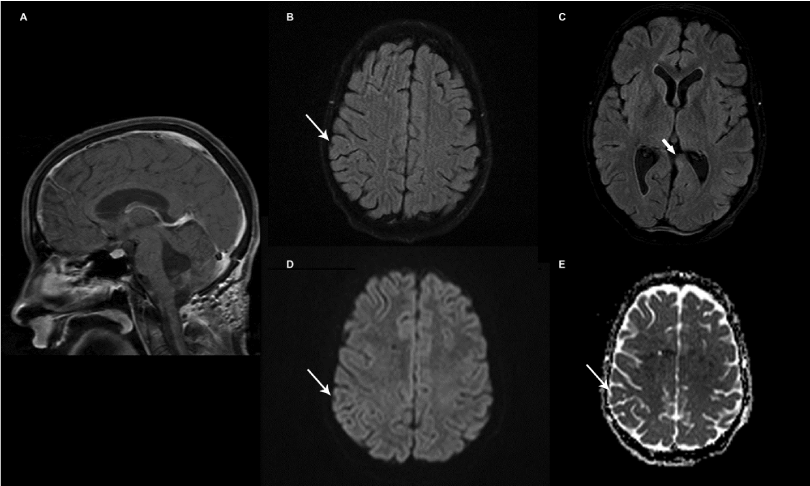

| Figure 2: Images from follow-up MRI study following surgical resection, chemotherapy and after completion of radiation therapy showing changes of surgical resection of posterior fossa mass (A). Axial FLAIR images showing resolution of the right parietal lesion (B-thin white arrow) and decreased conspicuity of the left medial temporal lesion (C-thick white arrow). No evidence of restricted diffusion in the location of the previously seen right parietal lesion on B=1000 diffusion image (D) and ADC map (E) consistent with resolution. |